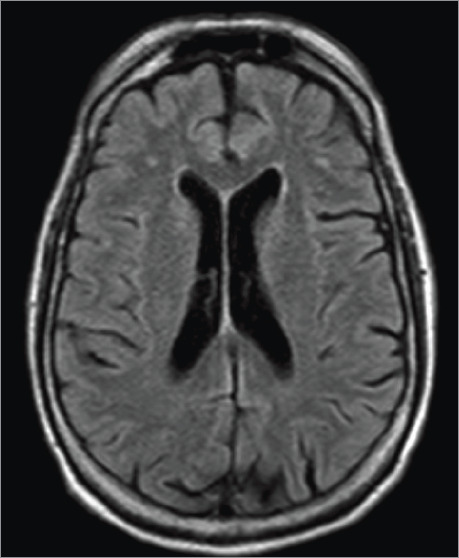

Acute transient contrast-induced neurologic deficit is an uncommon condition triggered by the administration of intra-arterial contrast during angiography. It can present with encephalopathy, cortical blindness, seizures, or focal deficits. This report describes a patient who presented with severe neurologic deficits after percutaneous coronary intervention, with complete symptom resolution within 72 hours.

Abstract Image